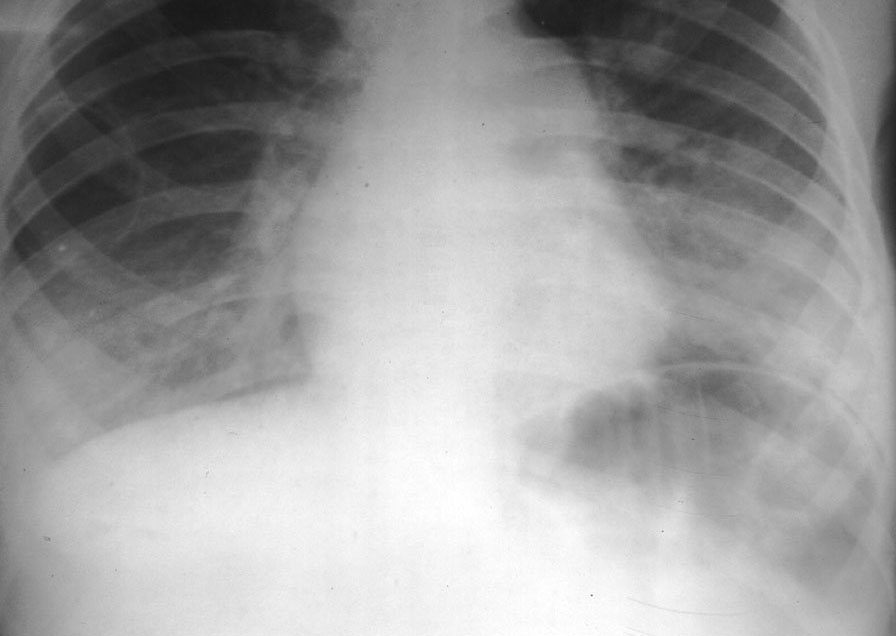

Mostly these lower respiratory infections include pneumonia and diseases of the lungs, tracheal tube etc. These diseases often spread by coughing, sneezing, laughing or exhaling. These diseases have an annual death toll of more than four million people.